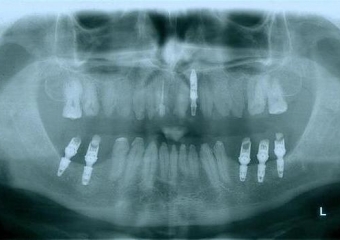

Raio - x inicial em 2014

Implantes instalados, em Setembro de 2014

Raio - x Próteses provisórias, em 2015